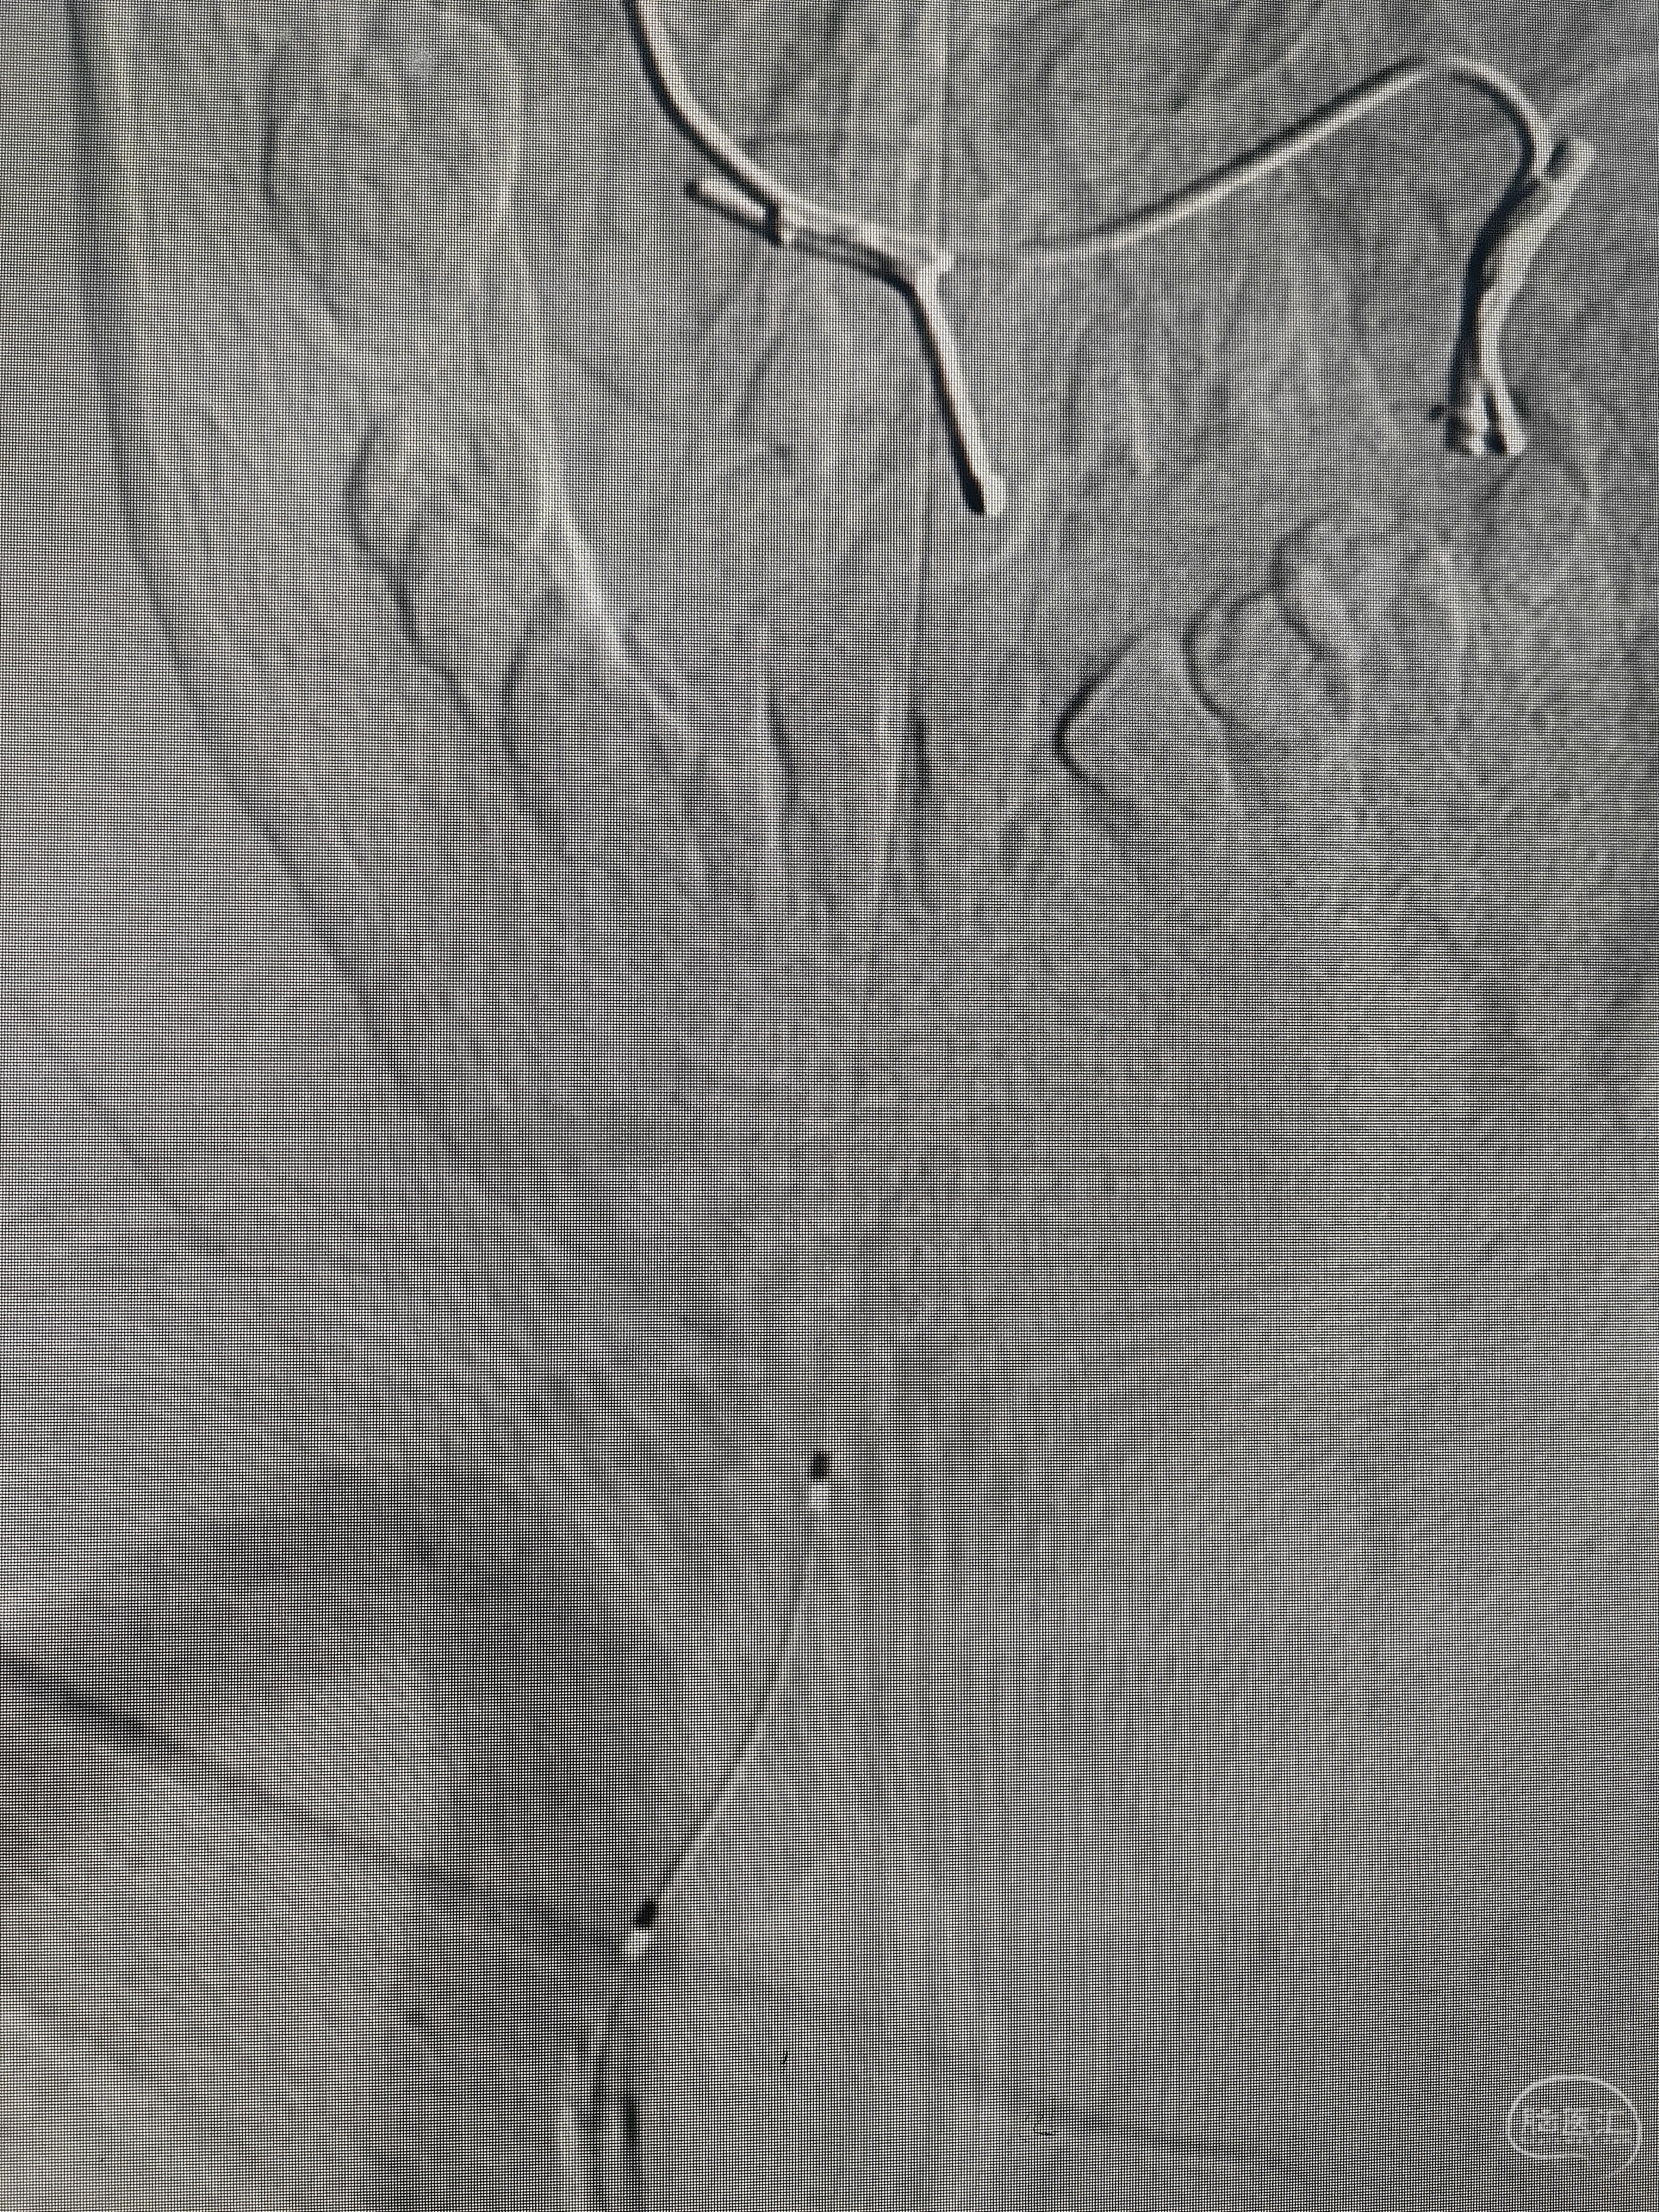

这是猪尾切了的样子